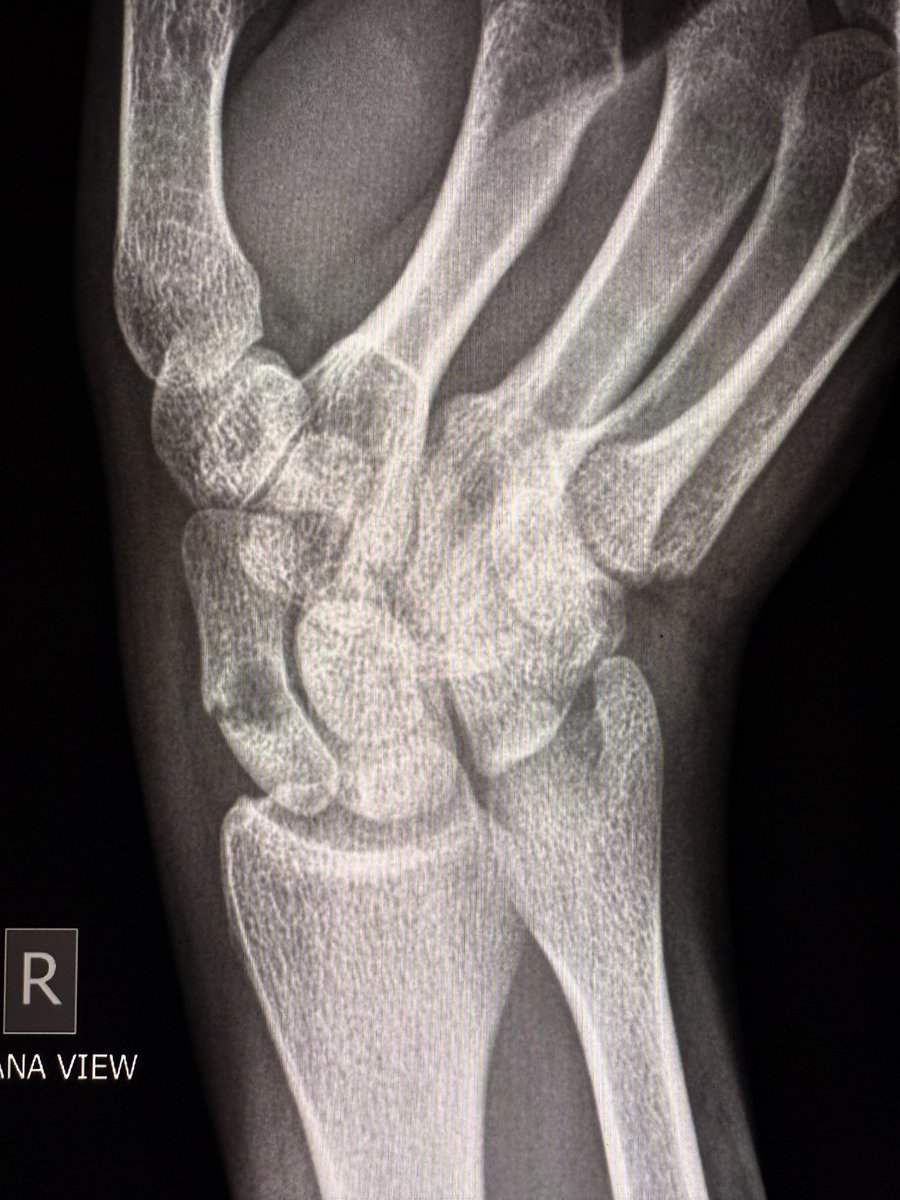

A large dorsal talar beak on sagittal CT or lateral ankle radiograph.

Talar beak is a marker of restricted subtalar motion, not a diagnosis. In a young patient, actively search for a subtalar coalition.

This case showed a fibrous coalition of Medial accessory talocalcaneal articulation at the level of the posterior sustentaculum tali, between the Talus and Calcaneus.

Wisdom: A talar beak should trigger a search, not end it.